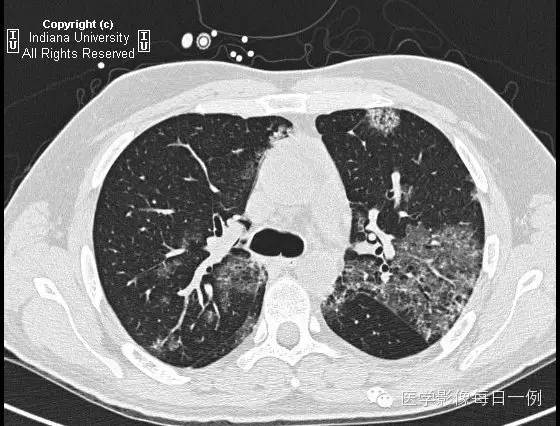

CT检查

【答案】2.D注释:支气管肺泡灌洗示肺出血,无合并性感染。

胸部CT示弥漫性肺泡透光度减低,主要位于右肺下叶和左肺上叶,呈铺路石样改变。胸膜无渗出。